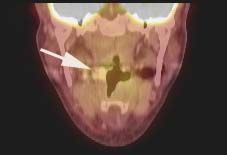

Led by Dr. Eri Srivatsan and Dr. Marilene Wang, UCLA Jonsson Comprehensive Cancer Center members and co-authors of the study, researchers found the link between the protein gigaxonin and head and neck cancer while investigating the chemotherapy drug cisplatin. The drug is successfully able to kill cancer cells by interacting with the protein p16 which is commonly produced in HPV-positive cancers.

“We studied the interaction of p16 in the nucleus of the cancer cell after treatment with cisplatin, and observed how the protein interacted with gigaxonin,” said Wang, professor-in-residence of head and neck surgery. “We found the combination of the proteins stops the cell cycle, allowing chemotherapy treatment to prevent the cell from growing and killing the cancer cell.”

For the study, Wang, Srivatsan and eight colleagues at UCLA also analyzed 103 archival clinical samples from head and neck cancer patients to identify the relationship between p16 nuclear expression and cancer-free survival. They found that patients with cancers with p16 expression had better survival rates than without p16 expression.